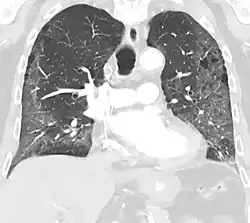

High-resolution CT image showing ground-glass opacities in the periphery of both lungs in a patient with COVID-19 (red arrows). The adjacent normal lung tissue with lower attenuation appears as darker areas.

Ground-glass opacity is among the most common imaging findings in patients with confirmed COVID-19.[16][17] One systematic review found that among patients with COVID-19 and abnormal lung findings on CT, greater than 80% had GGOs, with greater than 50% having mixed GGOs and consolidation.[16] GGOs with mixed consolidation has most often been found in elderly populations.[18] Several studies have described a pattern among initial, intermediate, and hospital discharge imaging findings in the disease course of COVID-19. Most commonly, initial CT imaging reveals bilateral GGOs at the periphery of the lungs. During initial stages, this is most often found in the lower lobes, although involvement of the upper lobes and right middle lobe has also been reported early in the disease course.[16][18] This is in contrast to the two similar coronaviruses, SARS and MERS, which more commonly involve only one lung on initial imaging.[19][20] As the COVID-19 infection progresses, GGOs typically become more diffuse and often progress to consolidation.[11][18] This is sometimes accompanied by the development of a crazy paving pattern and interlobular septal thickening.[18] In many cases the most severe pulmonary CT abnormalities occurred within 2 weeks after symptoms began.[17] At this point, many individuals begin showing resolution of consolidation and GGOs as symptoms improve. However, some patients have worsening symptoms and imaging findings, with further increase in septal thickening, GGOs, and consolidation. These patients may develop lung "white-out" with progression to acute respiratory distress syndrome (ARDS) requiring treatment escalation.[17][21]